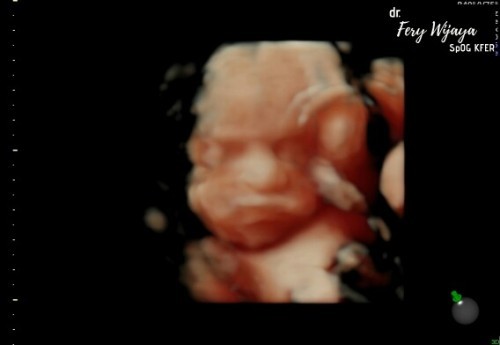

Bun mau nanya dong, aku lagi hamil 8week6day semalam kencing terus sampe tempat keluarnya kencing itu jadi sakit banget trus lama2 urine ada keluar warna pink dikit, trus kencing lagi eh urine udah sepenuhnya warna pink, dan waktu ke bidan katanya bahaya janinnya dan akhirnya di tespek masih positif, kata bidan janinnya terancam tapi aku engga begitu yakin karna dulu punya riwayat infeksi saluran kencing takutnya karna itu, sebelum hamil yg ini juga pernah keguguran jadi takut banget bun, aku harus ngapain kalo gini waswas banget 😭#seriusnanya #bantusharing #jangandibully #Nanya